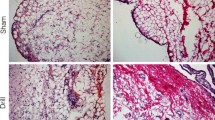

Morphologic description of H&E and Masson trichrome stained slides

Hematoxylin and eosin (H&E) staining confirmed that left (surgery sham control) knees retained the typical histological properties of IFP/SC, including mature adipocytes, a stromal vascular fraction, and white blood cells (predominantly large and small mononuclear cells consistent with macrophages and lymphocytes, respectively) (Fig. 2A, C). In contrast, the right (IFP/SC removal) hindlimbs exhibited a development of a thick band of dense fibrous connective tissue (FCT) in the space previously occupied by the native IFP/SC (Fig. 2B, D). Further histological examination with Masson trichrome stain confirmed the increased collagenous nature of the FCT compared to the native IFP (Fig. 2E, F; Supplemental Fig. 2). Notably, intact synovium as part of the IFP/SC was confirmed on histopathology for all limbs at termination.

Characterization of IFP/SC and replacement tissue. Representative mid-sagittal photomicrographs of a stifle joint from a control (A, E) and IFP/SC removal (B, F) guinea pig; H&E (A, B), and Masson’s trichrome (E, F), 2× objective. (A, C) Control knee joint from a 7-month-old guinea pig depicting the normal histoanatomic location of the IFP/SC in its native state. (B, D) Knee joint from 7-month-old guinea pig four months after IFP/SC removal. The IFP/SC (C) is replaced with dense fibrous connective tissue (FCT) 20× objective for the main photo; 10× objective for inset (D)